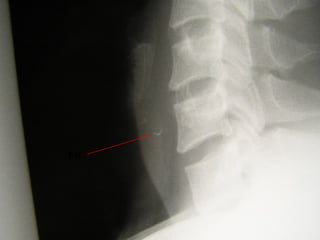

FB Throat - Investigations

Lateral neck XR

CXR

Barium swallow

CT scan – without contrast

Rigid oesophagoscopy

FB

Hyoid bone

Thyroid cartilage

Cricoid cartilage

Osteophyte

FB Throat

>50% of ingested FB cannot be found!

Discharge with symptomatic treatment

Cover with antibiotics if diabetic patient or

immunocompromised

FB advice

Chest pain, fever, increasing symptoms